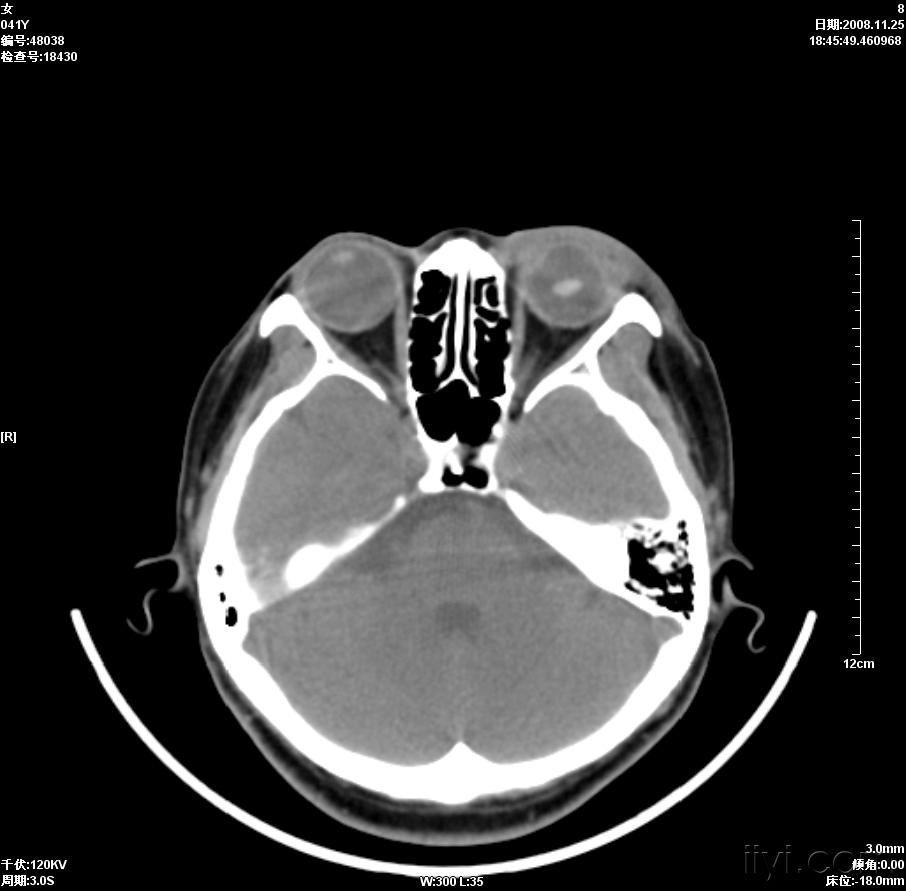

晶状体移位ct病例